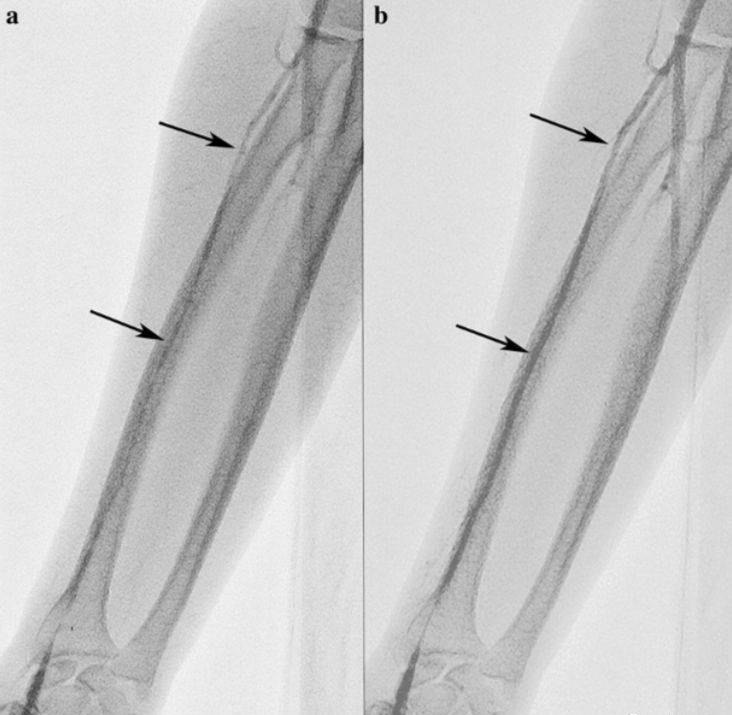

桡动脉穿刺完成后,会通过上肢动脉送入导引导丝和造影导管进入心脏。个别的患者上肢动脉存在先天迂曲、狭窄,或者某些原因诱发血管痉挛,导丝或导管通过时会牵拉甚至损伤动脉血管,从而出现疼痛。这种疼痛一般是短暂的,器械通过迂曲或狭窄处后症状就会消失,也不会留下什么后遗症。

但是,如果造成血管壁破裂出血,局部组织血肿,不适感就只能等伤口完全愈合后才能消失。